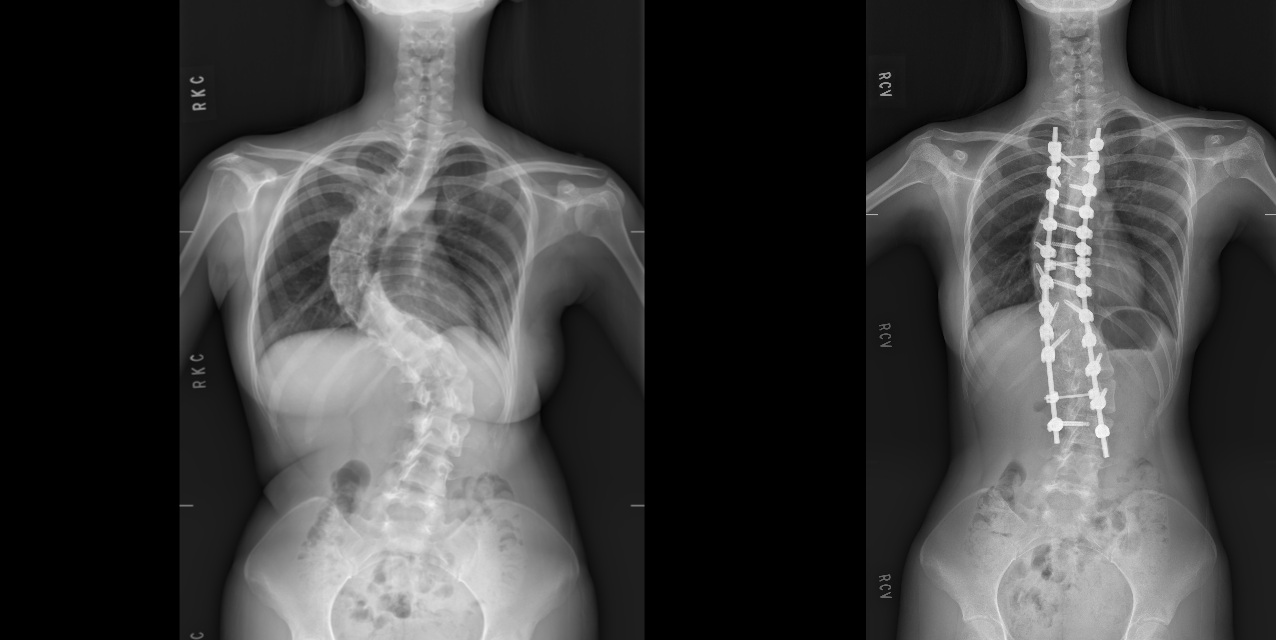

術前及術後對照X光片。

【賴傳媒 記者爆料網 蔡智銘/台中報導】黃姓女僑生(今年21歲,手術時18歲)因嚴重脊椎側彎,導致心肺功能受壓迫,稍微一活動就會喘,呼吸困難,嚴重影響生活和外觀,為了遮掩不好看的背部,她一直穿寬鬆的衣服、出門一定穿外套,也留長髮遮掩,直到來台求學時,脊椎問題越發嚴重,到臺中榮總就醫照X光驚覺脊椎彎曲已達90度,電腦斷層影像如同一隻蜈蚣盤據在背部。

臺中榮總骨科部脊椎外科主任潘建州說明,黃同學脊椎側彎最嚴重是在胸椎處。